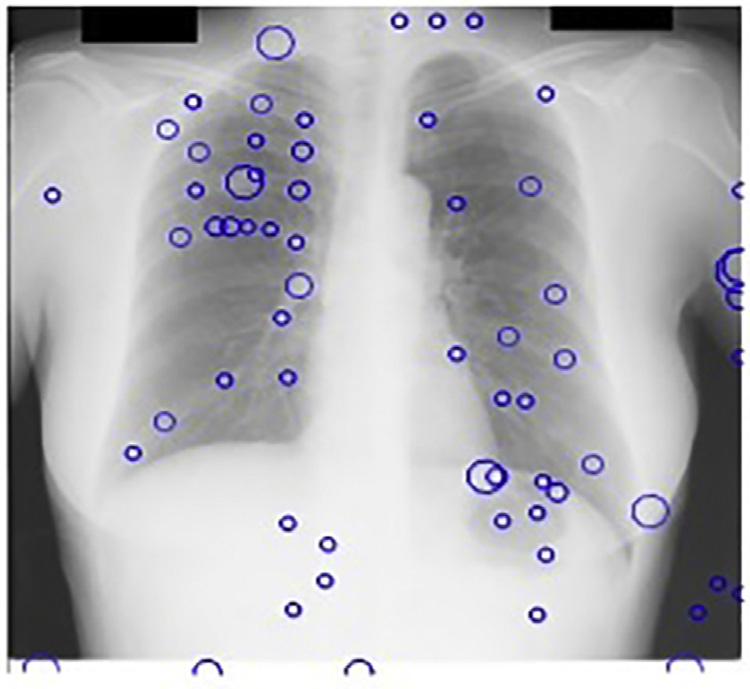

斑点检测器以JSRT数据库的X光图像作为输入。我们的多尺度斑点检测系统每幅图像平均检测到218个结节。由于在此阶段遗漏的任何真阳性在后续阶段都无法恢复,因此在获取多尺度LOG滤波器输出中的局部最大值时设置了较低的阈值。图14.17显示了基本CAD方案中我们的斑点检测器的输出。

观察到,在我们的尺度空间图像中,68%的这些假阳性出现在前几个精细尺度上。

这些尺度存在大量高频噪声;因此,在从检测到的多尺度输出中选取最佳拉普拉斯‐高斯滤波响应时,可以安全地忽略这些尺度。这些响应作为kNN分类的种子点,如图14.15所示。仅保留最强的候选点。

作为我们CAD方案的第一后处理步骤,移除了142个假阳性。在JSRT数据库中这些尺度下没有候选结节,因此真阳性未减少。图14.18显示了我们的CAD方案的输出,其中前几个精细尺度的输出被忽略。